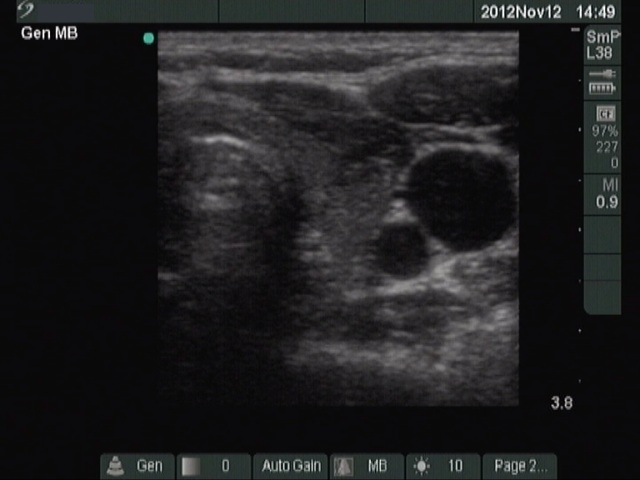

Follow-up examination 21 months after initial investigation (fourth row of images):

Clinical presentation: The patient had no complaints.

Palpation: no abnormality.

Functional state: euthyroidism with TSH-level 1.78 mIU/L.

Ultrasonography: The pattern has become completely echonormal. There were no significant change in the vascularization.